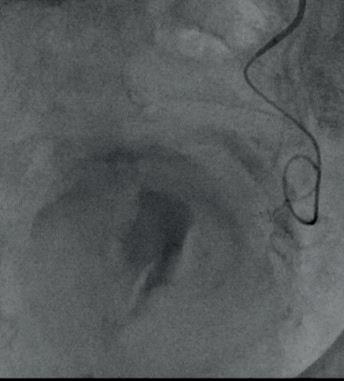

The focus of their study was to establish the role of IR in the management of potentially lifethreatening postpancreatectomy complications such as PPH, thus preventing re-exploration. To do so, Kulkarni and colleagues enrolled 758 patients who underwent pancreatic surgery between January 2014 and December 2019. All patients who developed post-surgical complications within 90 days of primary hospitalisation were included. Complications were classified according to the International Study Group of Pancreatic Surgery (ISGPS).

The types of surgery included in the study were pancreatectomy (4%), pancreaticoduodenectomy (73.8%), enucleation (1%), pancreatectomy and vein resection (4.85%), and multivisceral pancreatic surgery (16.5%). Of the 758 patients included, 206 (27.2%) developed post-surgical complications. Of these, 46 patients (6%) experienced PPH, with 30 patients (3.96%) requiring intervention; 13 patients (43.3%) underwent angioembolization, of whom five (38.46%) died due to causes unrelated to PPH, while 17 patients (56.7%) underwent surgical reexploration.

The authors note that the 90-day mortality rate in patients with PPH was 17.39%, which is comparable

with other studies in the literature. For patients who underwent primary angioembolization for PPH, the mortality rate was 38.46%—which is not statistically significant, they detail. The causes of death for these five patients included biliary sepsis with multiorgan dysfunction, myocardial infarction, hepatic decompensation, and major hepaticojejunostomy and pancreatojejunostomy leaks. Kulkarni and colleagues state that “although PPH may have been a contributing factor, the causes of death were not directly related to the condition”.

“Image-guided interventions successfully prevented re-exploration in 61.5% of PPH cases, 88.9% of biliary complications, and 99.3% of intra-abdominal fluid collections,” state Kulkarni et al, emphasising the “pivotal role” IR plays in managing post-surgical complications.

“IR provides a minimally invasive alternative to surgical re-exploration, reducing recovery time and preventing morbidity associated with re-exploration,” say the authors. They highlight that “early recognition and prompt intervention” are key in patients with PPH, biliary leak and portal vein thrombosis, as these are conditions associated with high mortality and morbidity rates. However, in cases where surgical re-exploration is required, this is “often due to complications which are beyond the scope of percutaneous management”, Kulkarni et al point out.